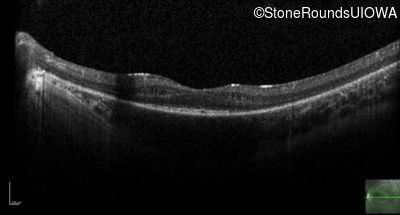

Optical Coherence Tomography - Right - 20/60

Exemplar / OCT Stack

Optical Coherence Tomography - Left - 20/70